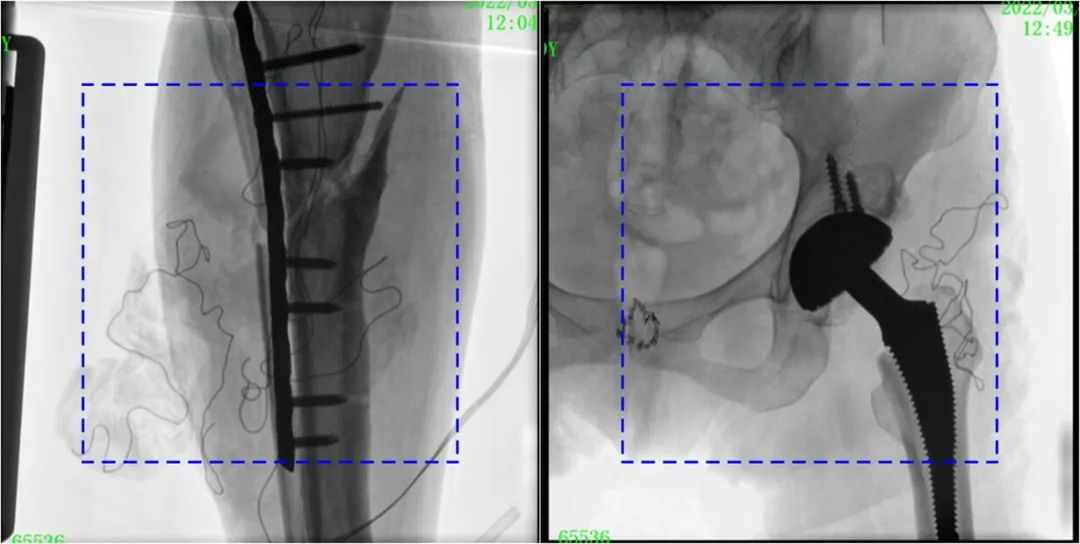

與傳統(tǒng)的21CM×21CM成像尺寸相比,普愛醫(yī)療大平板一體式C形臂具有30CM×30CM更大成像尺寸,能夠一次成像5.5節(jié)椎體,呈現(xiàn)更全面的影像信息,即便是手術(shù)經(jīng)驗不豐富的年輕醫(yī)生也能通過圖像迅速判斷椎體節(jié)段、定位手術(shù)部位,避免因為視野不足而造成的多次定位、反復(fù)曝光,提高效率的同時避免過量攝入輻射。

普愛醫(yī)療大平板一體式C形臂圖像與傳統(tǒng)圖像對比(藍色虛線內(nèi)為傳統(tǒng)21CM×21CM平板的成像區(qū)域)